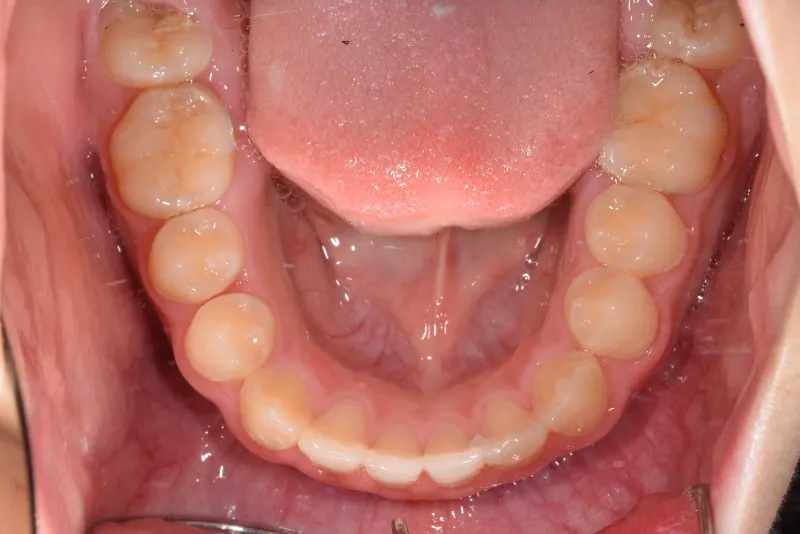

永久歯に生え変わってからはマルチブラケット装置を使用し、噛み合わせ・見た目をしっかり仕上げました。

治療回数42回、4年6ヶ月の治療期間で矯正治療を終了しました。

主訴が改善され、ご満足頂きました。